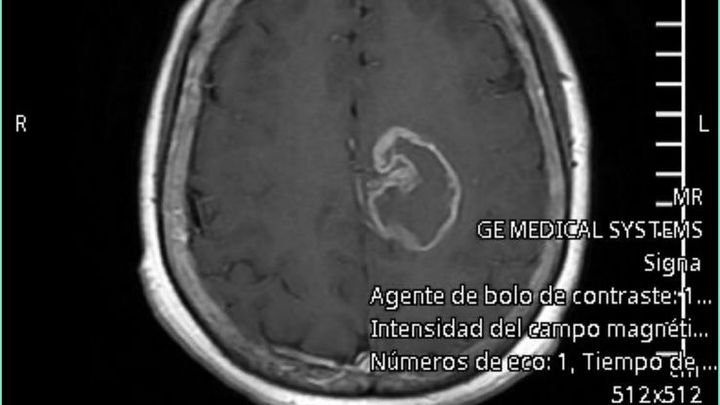

Mi mamá es una mujer fuerte, valiente y llena de vida. También mi mejor amiga. Hace poco nos dieron una noticia que partió nuestra vida en dos: le diagnosticaron glioblastoma multiforme, un tumor cerebral agresivo que afectó el lado izquierdo de su cerebro. Desde entonces, nuestra vida se ha convertido en una batalla diaria por su salud.

My mom is a strong, brave, and full of life woman and also my best friend. Not long ago, we received news that changed our lives forever: she was diagnosed with glioblastoma multiforme, an aggressive brain tumor that affected the left side of her brain. Since then, our lives have become a daily battle for her health.